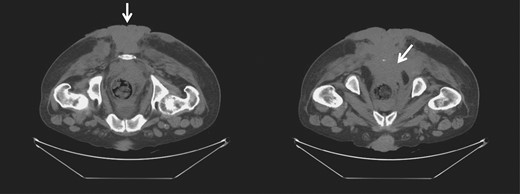

While neoadjuvant chemoradiotherapy, with 5-fluorouracil, mitomycin-C and radiation dose of 45 Gy, at pelvic, perianal and gluteal regions was started, the patient was lost in follow-up. He was readmitted 2 months later for trouble controlling bowels, for which he underwent diverting colostomy. There was significant necrosis of the tumor (Fig. 2), and the biopsy showed with mild to moderate dysplasia. A wide local excision and debridement of the soft tissue were performed down to presacral fascia and gluteal fascia on right and left buttocks.

Gross image (A) and CT of the pelvis and perineum (B) showing exacerbation of the tumor with significant necrosis and invasion into the rectum and anal canal.